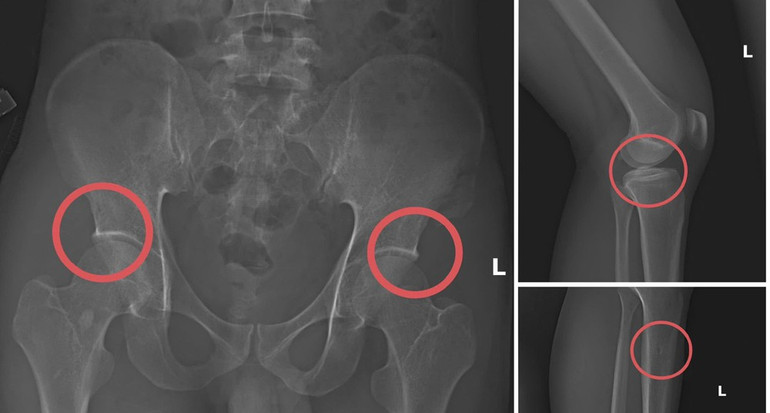

Theo Công an tỉnh Phú Thọ, đường dây do Tạ Minh Châu (SN 1996), nguyên cán bộ Trung tâm Y tế huyện Cẩm Khê cầm đầu. Lợi dụng thời gian dài công tác trong ngành và am hiểu cấu trúc xương khớp, Châu đã xây dựng quy trình trục lợi khép kín, gồm vận động người mua bảo hiểm, trực tiếp gây thương tích bằng thuốc mê và các dụng cụ tác động lực, sau đó dựng hiện trường giả để hợp thức hóa hồ sơ điều trị.

Châu trực tiếp tiêm thuốc mê rồi dùng kim tiêm, búa tác động vào xương người mua bảo hiểm, tạo các vết vỡ xương tương tự tai nạn. Sau đó, các đối tượng được hướng dẫn dựng hiện trường giả như điện giật ngã, trượt chân ngã suối để hợp thức hóa bệnh án và hoàn thiện hồ sơ yêu cầu chi trả.